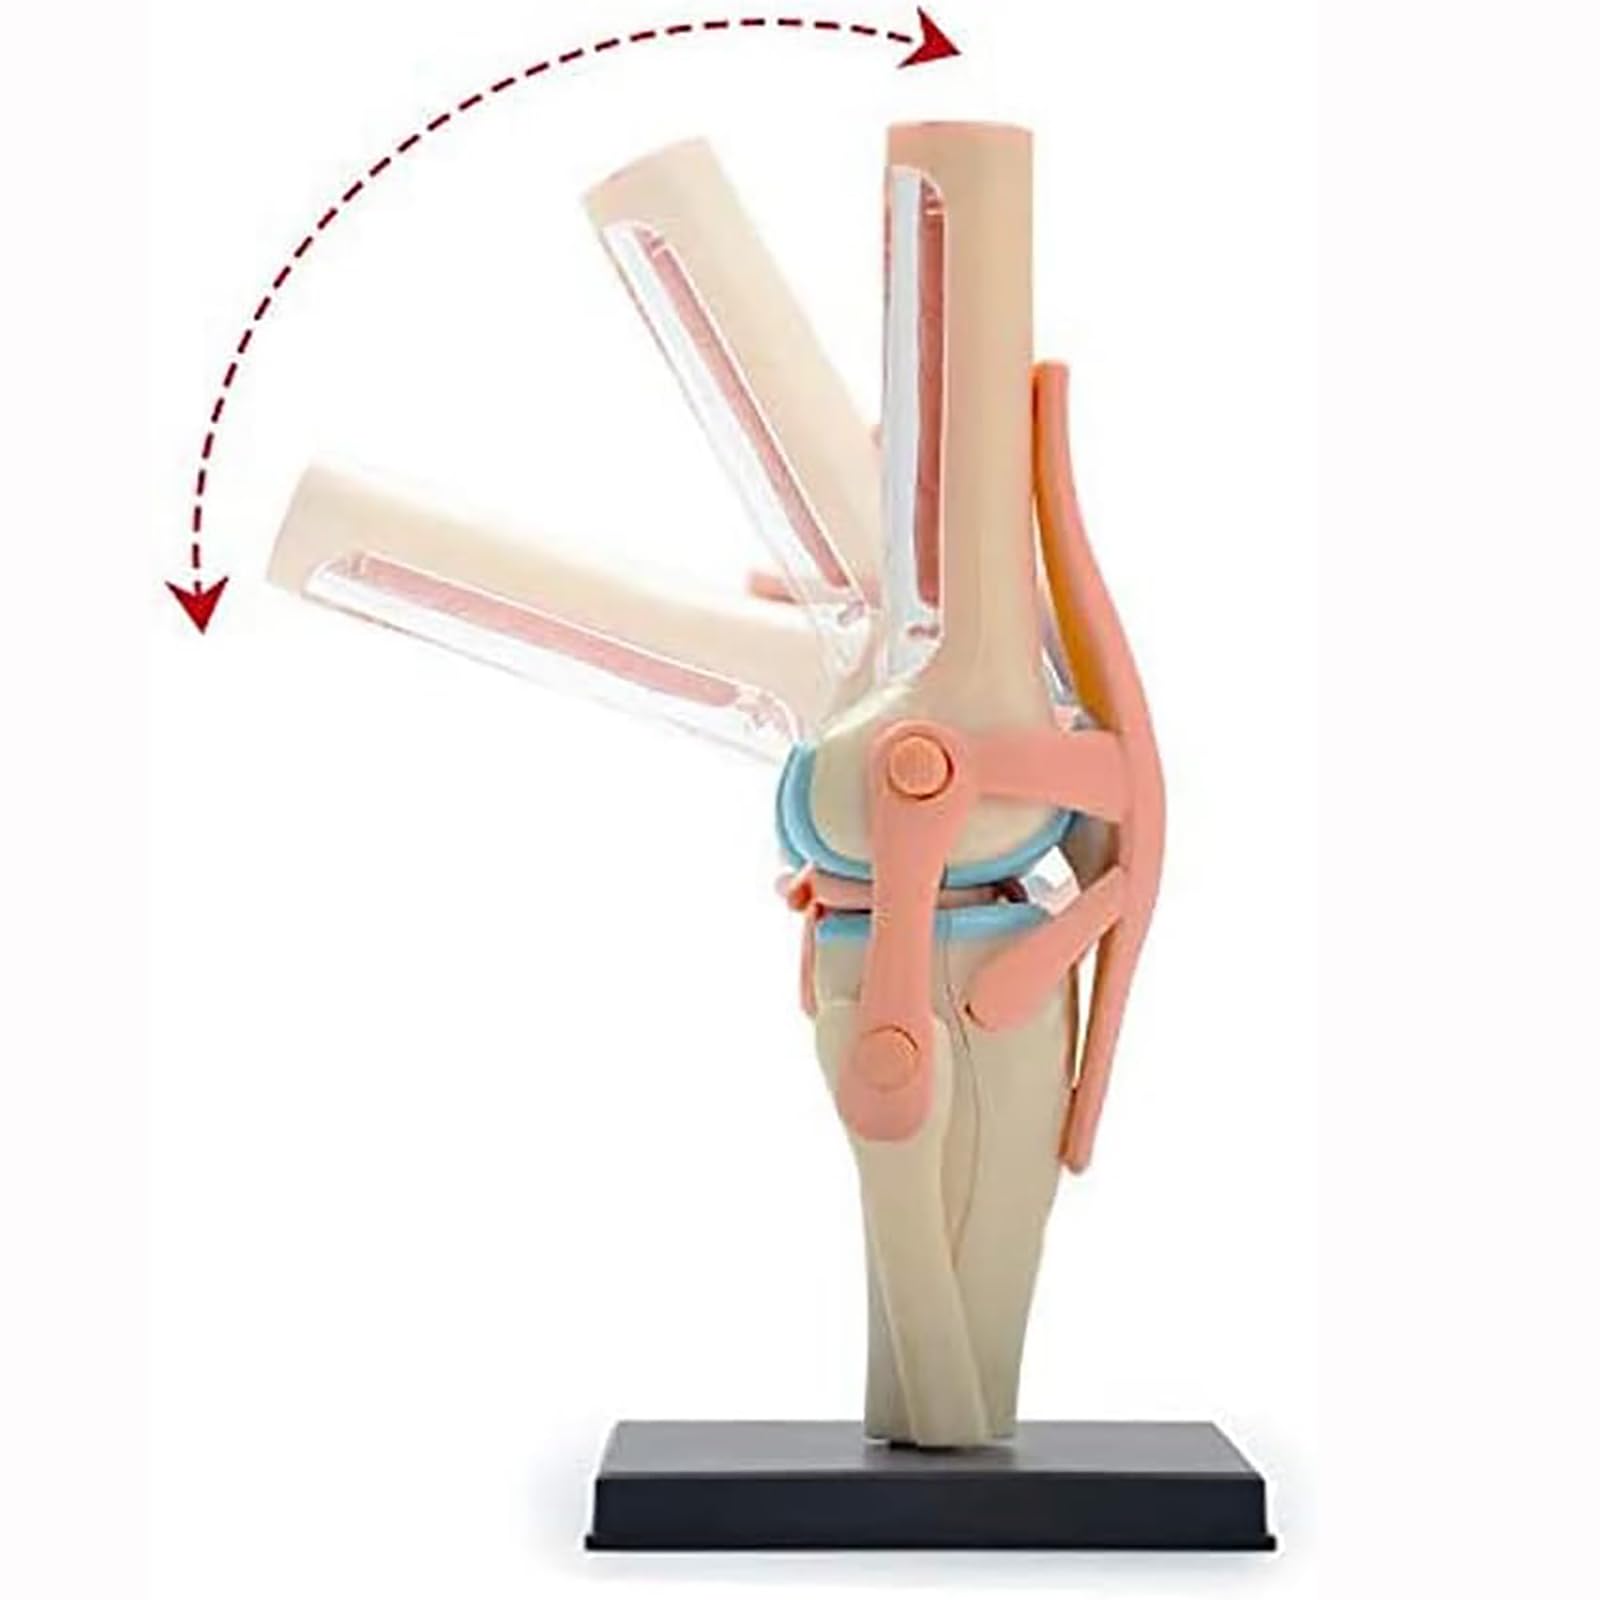

UNbit Anatomical Model of Human Knee Joint Organs 4D Model of Human Knee Articulation 23 Detachable Parts Model of Medical Teaching for Medical Education

UNbit Anatomical Model of Human Knee Joint Organs 4D Model of Human Knee Articulation 23 Detachable Parts Model of Medical Teaching for Medical Education

This anatomical model aids in the study of human biology and anatomy by providing a hands-on, 3D representation of the knee joint.